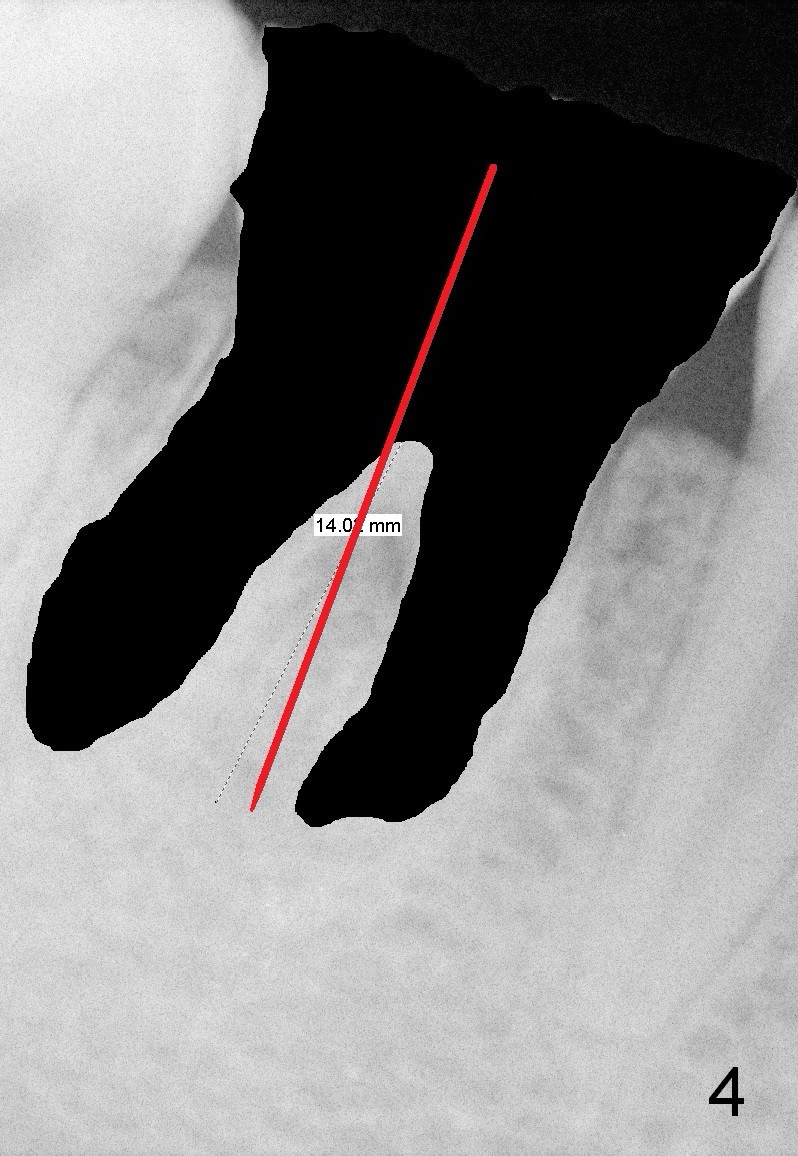

First of all, use a sharp small pilot drill (1.2, 1.5 or 2.0 mm) 3 mm shy of the extended length. For this case, the initial depth will be 14 mm from the gingival margin (Fig.3: red long arrow). If the drill is straight and in the middle of the septum (1st intraop PA), keep drilling for the next 3 mm. If the trajectory is off (Fig.4), withdraw the drill (Fig.5 black long arrow), find a new starting point, change the trajectory and finish osteotomy depth (red long arrow) if the new trajectory is deemed correct. Take more X-ray if necessary.